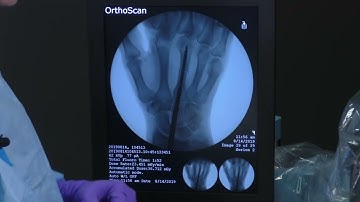

Development and Implementation of Intramedullary Screw Fixation in Metacarpal Shaft Fractures